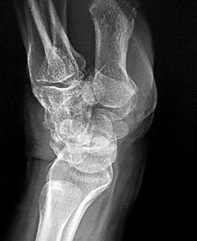

A 32-year-old male sustains a Hawkins Type III talar neck fracture following a high-speed motor vehicle collision. Which of the following accurately describes the displacement pattern and the approximate historical risk of avascular necrosis (AVN) for this specific injury type?

Explanation

Hawkins Type III is a displaced talar neck fracture with dislocation of both the subtalar and tibiotalar joints. The risk of AVN in Type III fractures is exceptionally high, historically reported as up to 100% (though modern series may show ~85-90%). Type I is nondisplaced (~0-15% AVN). Type II has subtalar dislocation (~20-50% AVN). Type IV involves the talonavicular joint in addition to the subtalar and tibiotalar joints.